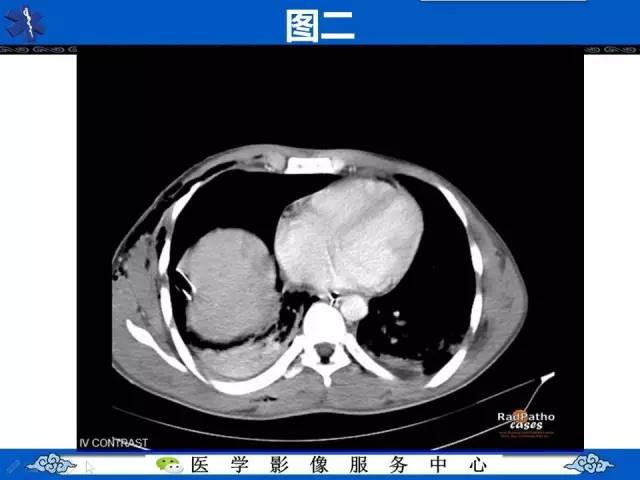

圆锥面包征——膈肌破裂

【影像征象】圆锥面包征——膈肌破裂